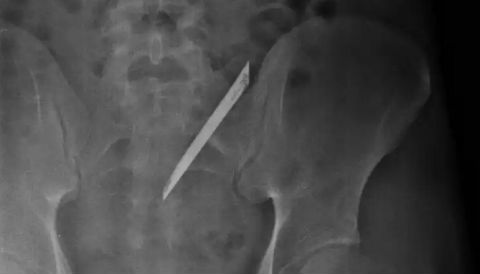

10 phút sau khi bị con dao găm vào lưng, người đàn ông được đưa vào bệnh viện cấp cứu. Kết quả chụp X-quang, lưỡi dao đi vào vùng cột sống ngực, nằm chồng lên bóng tim.